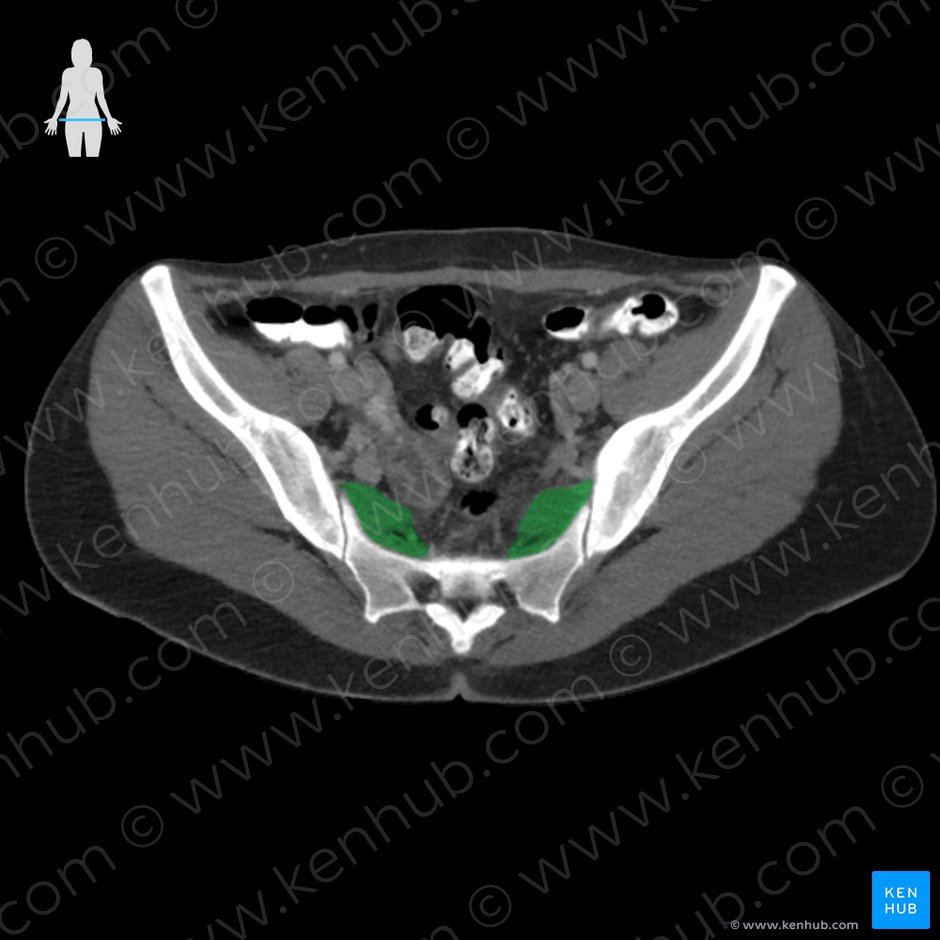

Piriformis Trigger Point Diagram 이상근의 TrPs의 경우 방사통은 천장관절부로 방사되기도 하며,

외측으로는 둔부 중앙을 넘어 고관절 후부와 대퇴 후부의 근위부 2/3로 방사됩니다.